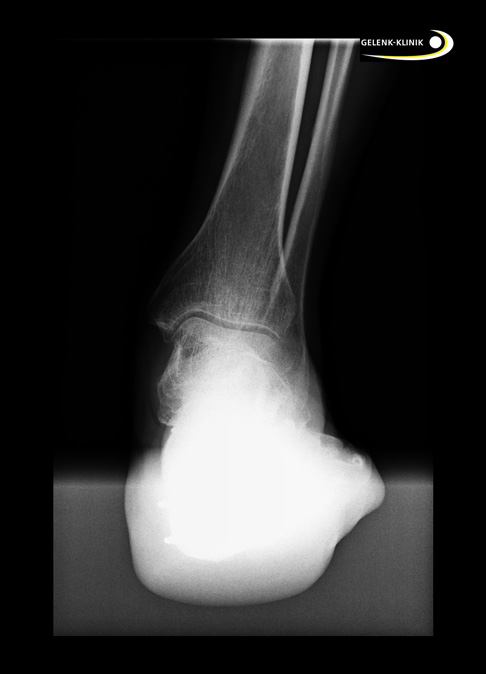

Bildgebende Verfahren wie Röntgen unter Belastung (während der Patient also mit seinem vollen Gewicht auf dem Fuß steht) helfen, die Schäden nach einer Fersenbeinfraktur abzuklären. Diese Röntgen-Untersuchung im Stehen ist natürlich erst nach Ausheilung der Fersenbeinfraktur möglich.

Bei den Untersuchungen im Stehen sollten die Rückfußstellung in der Saltzmannaufnahme ebenso wie die Veränderung der Ferse in der Ansicht von oben (sog. axiale Aufnahme) geröntgt werden. Zudem wird der stehende Fuß seitlich geröntgt.

Die Stellung der Nachbarknochen (vor allem das Sprungbein) nach der Fersenbeinfraktur wird hier direkt beurteilt.